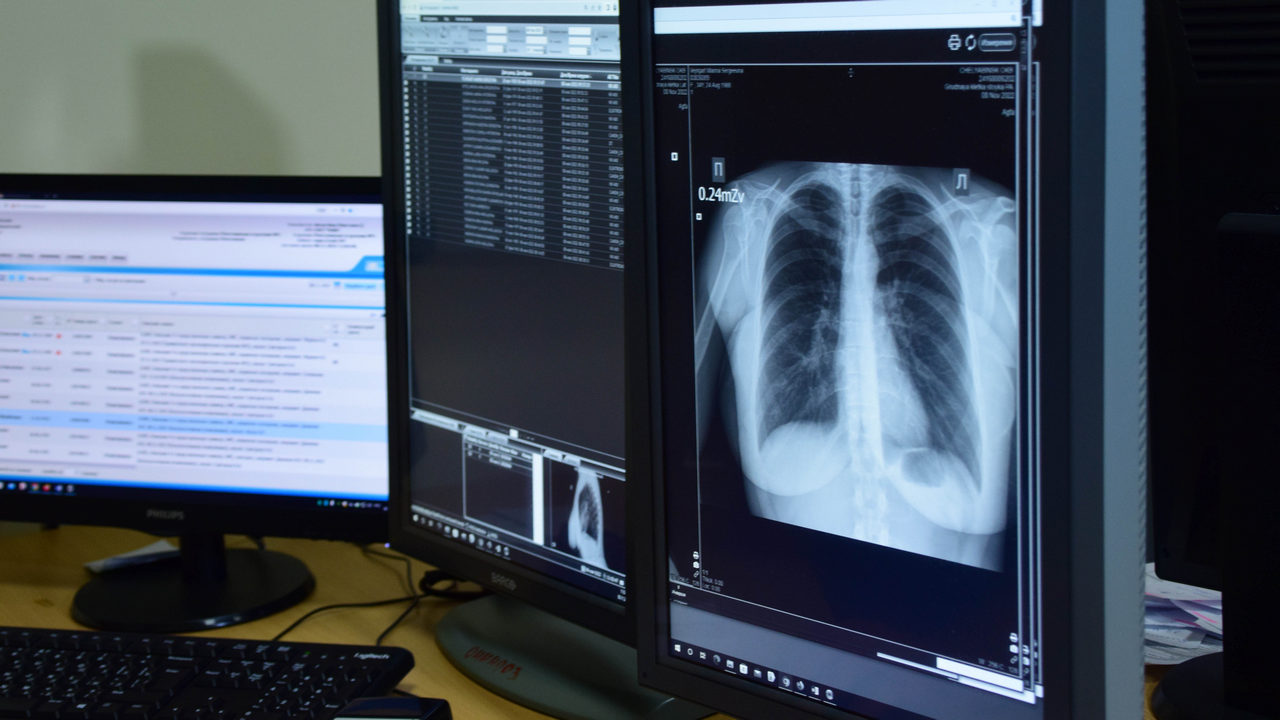

Долгий кашель может быть признаком серьезных болезней. Это патологии ЛОР-органов, сосудов и сердца, желудка или кишечника. Но чаще, как отмечает пульмонолог, проблема кроется в органах дыхания.

Анна Королева рекомендует не затягивать с походом к врачу, иначе возможны осложнения. Специалист выслушает жалобы пациента, направит его на обследование и на основании диагноза назначит лечение.